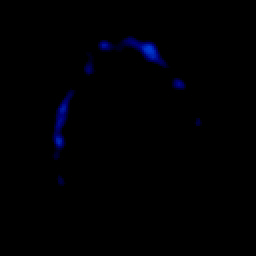

glioma overlay -- Slice #25

[Home][Help][Clinical] Slice 25